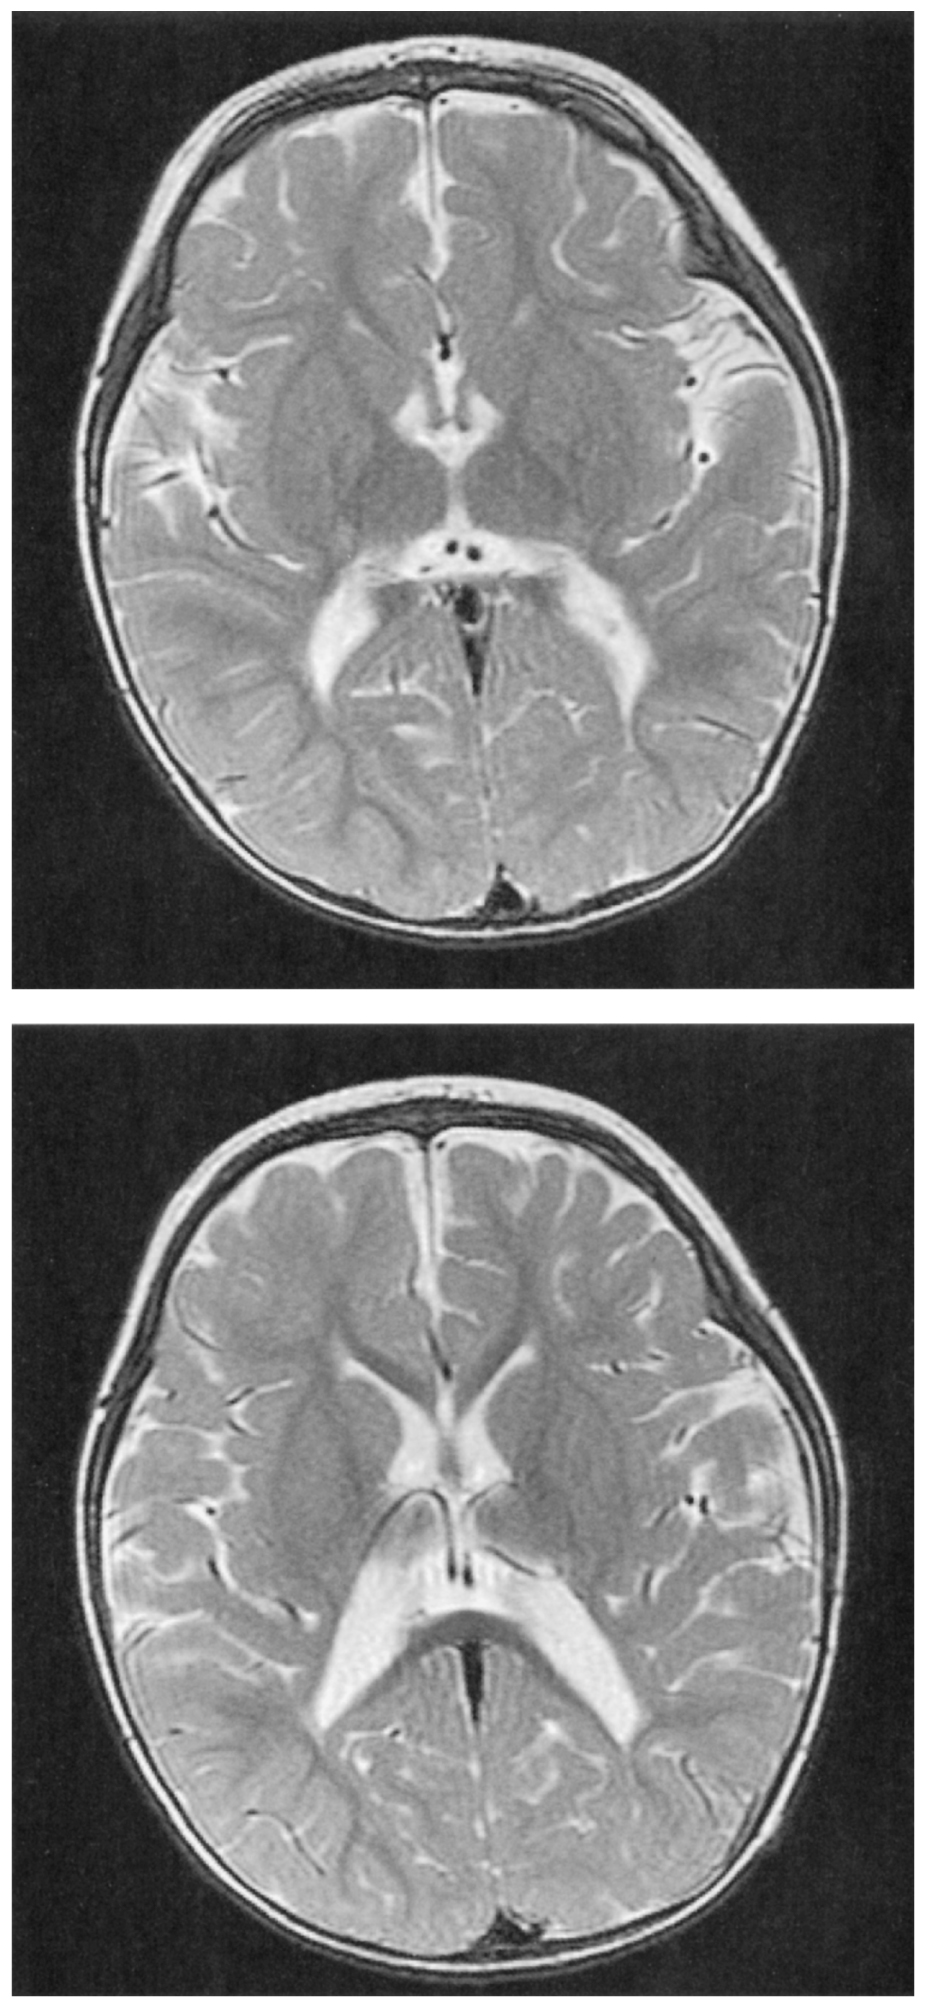

2歳の女児。早産児の定期外来のため母親に連れられて来院した。出生歴は,在胎29週,体重1,020g,Apgarスコアは7点(1分),8点(5分)で出生した。NICUに約4か月間入院した。入院中に光線療法を2日間行った。退院後は外来で定期的に経過観察されており,独歩がまだできない。意識は清明。身長82cm,体重10.5kg。体温37.1℃。脈拍112/分,整。呼吸数26/分。SpO2 98%(room air)。頭囲の拡大は認めない。心音と呼吸音とに異常を認めない。腹部は平坦,軟で,肝・脾を触知しない。皮膚に異常を認めない。下肢に筋緊張と腱反射の亢進を認め,尖足位である。Babinski徴候は陽性である。頭部単純MRIのT2強調像を下に示す。